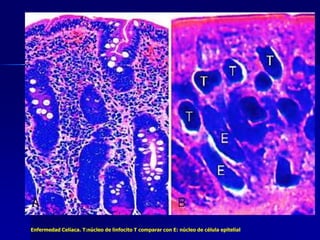

Enfermedad Celíaca. T:núcleo de linfocito T comparar con E: núcleo de célula epitelial

Enfermedad Celíaca. T:núcleode linfocito T comparar con E: núcleo de célula epitelial

 La enfermedad celiaca: trastorno

inflamatorio mediado por linfocitos T.

Mejora con la restricción del trigo en la dieta

(gliadina)

*La biopsia intestinal es fundamental para el diagnóstico y muestra cambios

típicos en la mucosa, que se pueden revertir con una dieta exenta de gluten.